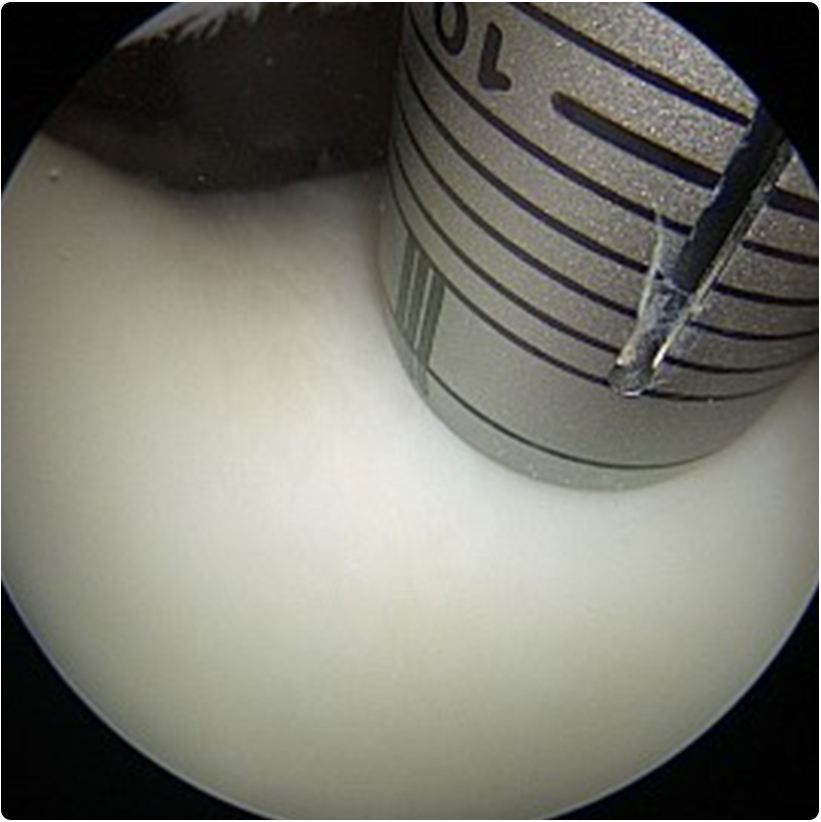

1- Artroskopik eklem debridmanı: özellikle küçük ve tam kat olmayan kıkırdak kayıplarında kapalı bir yöntemle 2-3 küçük delikten girilip kamera eşliğinde eklem içi gözlenir, kıkırdağın düzensiz ve hareketli bölümü özel traşlayıcı ve radyofrekans cihazı kullanılarak temizlenir ve daha düz bir yüzey elde edilmeye çalışılır. Bu yöntemle aynı anda eklem içindeki diğer sorunlar (örneğin menisküs  veya bağ yırtıkları) da aynı anda tedavi edilebilir.

2- Mikrokırık yöntemi: yine artroskopik olarak yapılabilen bu yöntemde kıkırdaktaki hasarlı alanlar temizlenir ve kıkırdağın altındaki kemiğe özel

aletlerle delikler açılır. Böylece kemik iliğinden gelen kan, pıhtı ve birçok hücreye dönüşme yeteneğindeki kök hücreler hasarlı alanı doldurabilir. Bir süre sonra orijinal kıkırdak dokusu kadar güçlü olmasa da ona benzeyen bir dokuyla çukur doldurulmuş olur.  Bu girişim yük taşıyan bir alana uygulandı ise 4-6 hafta kadar yük vermeyi kısıtlayan bir fizyoterapi uygulanır.